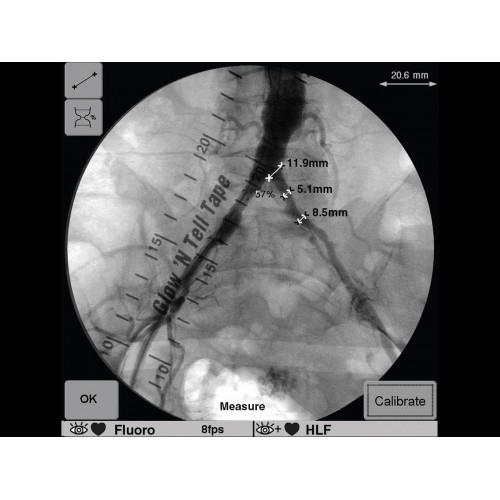

• Исключительное качество изображения для точного контроля операций

• Мощная система обработки изображений в реальном времени

GE OEC 9900 Elite оснащен революционной системой визуализации, обеспечивающей кристально четкое изображение анатомических структур. Интеллектуальная система автоматически адаптирует параметры исследования под конкретную хирургическую задачу, обеспечивая оптимальный баланс между качеством изображения и лучевой нагрузкой. Особое внимание уделено удобству работы операционной бригады.

В операционной практике GE OEC 9900 Elite демонстрирует исключительную эффективность при проведении сложных малоинвазивных процедур. Оборудование позволяет значительно сократить время вмешательства и повысить его безопасность для пациента. Многие хирурги отмечают улучшение точности операций и комфорт работы с системой.